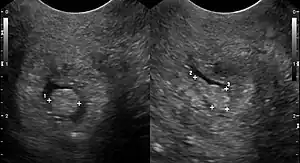

![]() | |

| Cervical polyp on ultrasound | |